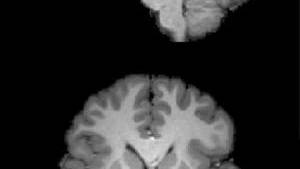

The fMRI scans showed that the anticipation of math caused a response in the brain similar to physical pain. The higher a person’s anxiety about math, the more anticipating math activated the posterior insula -- a fold of tissue located deep inside the brain just above the ear that is associated with registering direct threats to the body as well as the experience of pain. Interestingly, math anxiety levels were not associated with brain activity in the insula or in any other neural region when volunteers were doing math.

UChicago researchers have found that the higher a person’s anxiety about math, the more anticipating math activated areas of the brain related to experiencing pain.